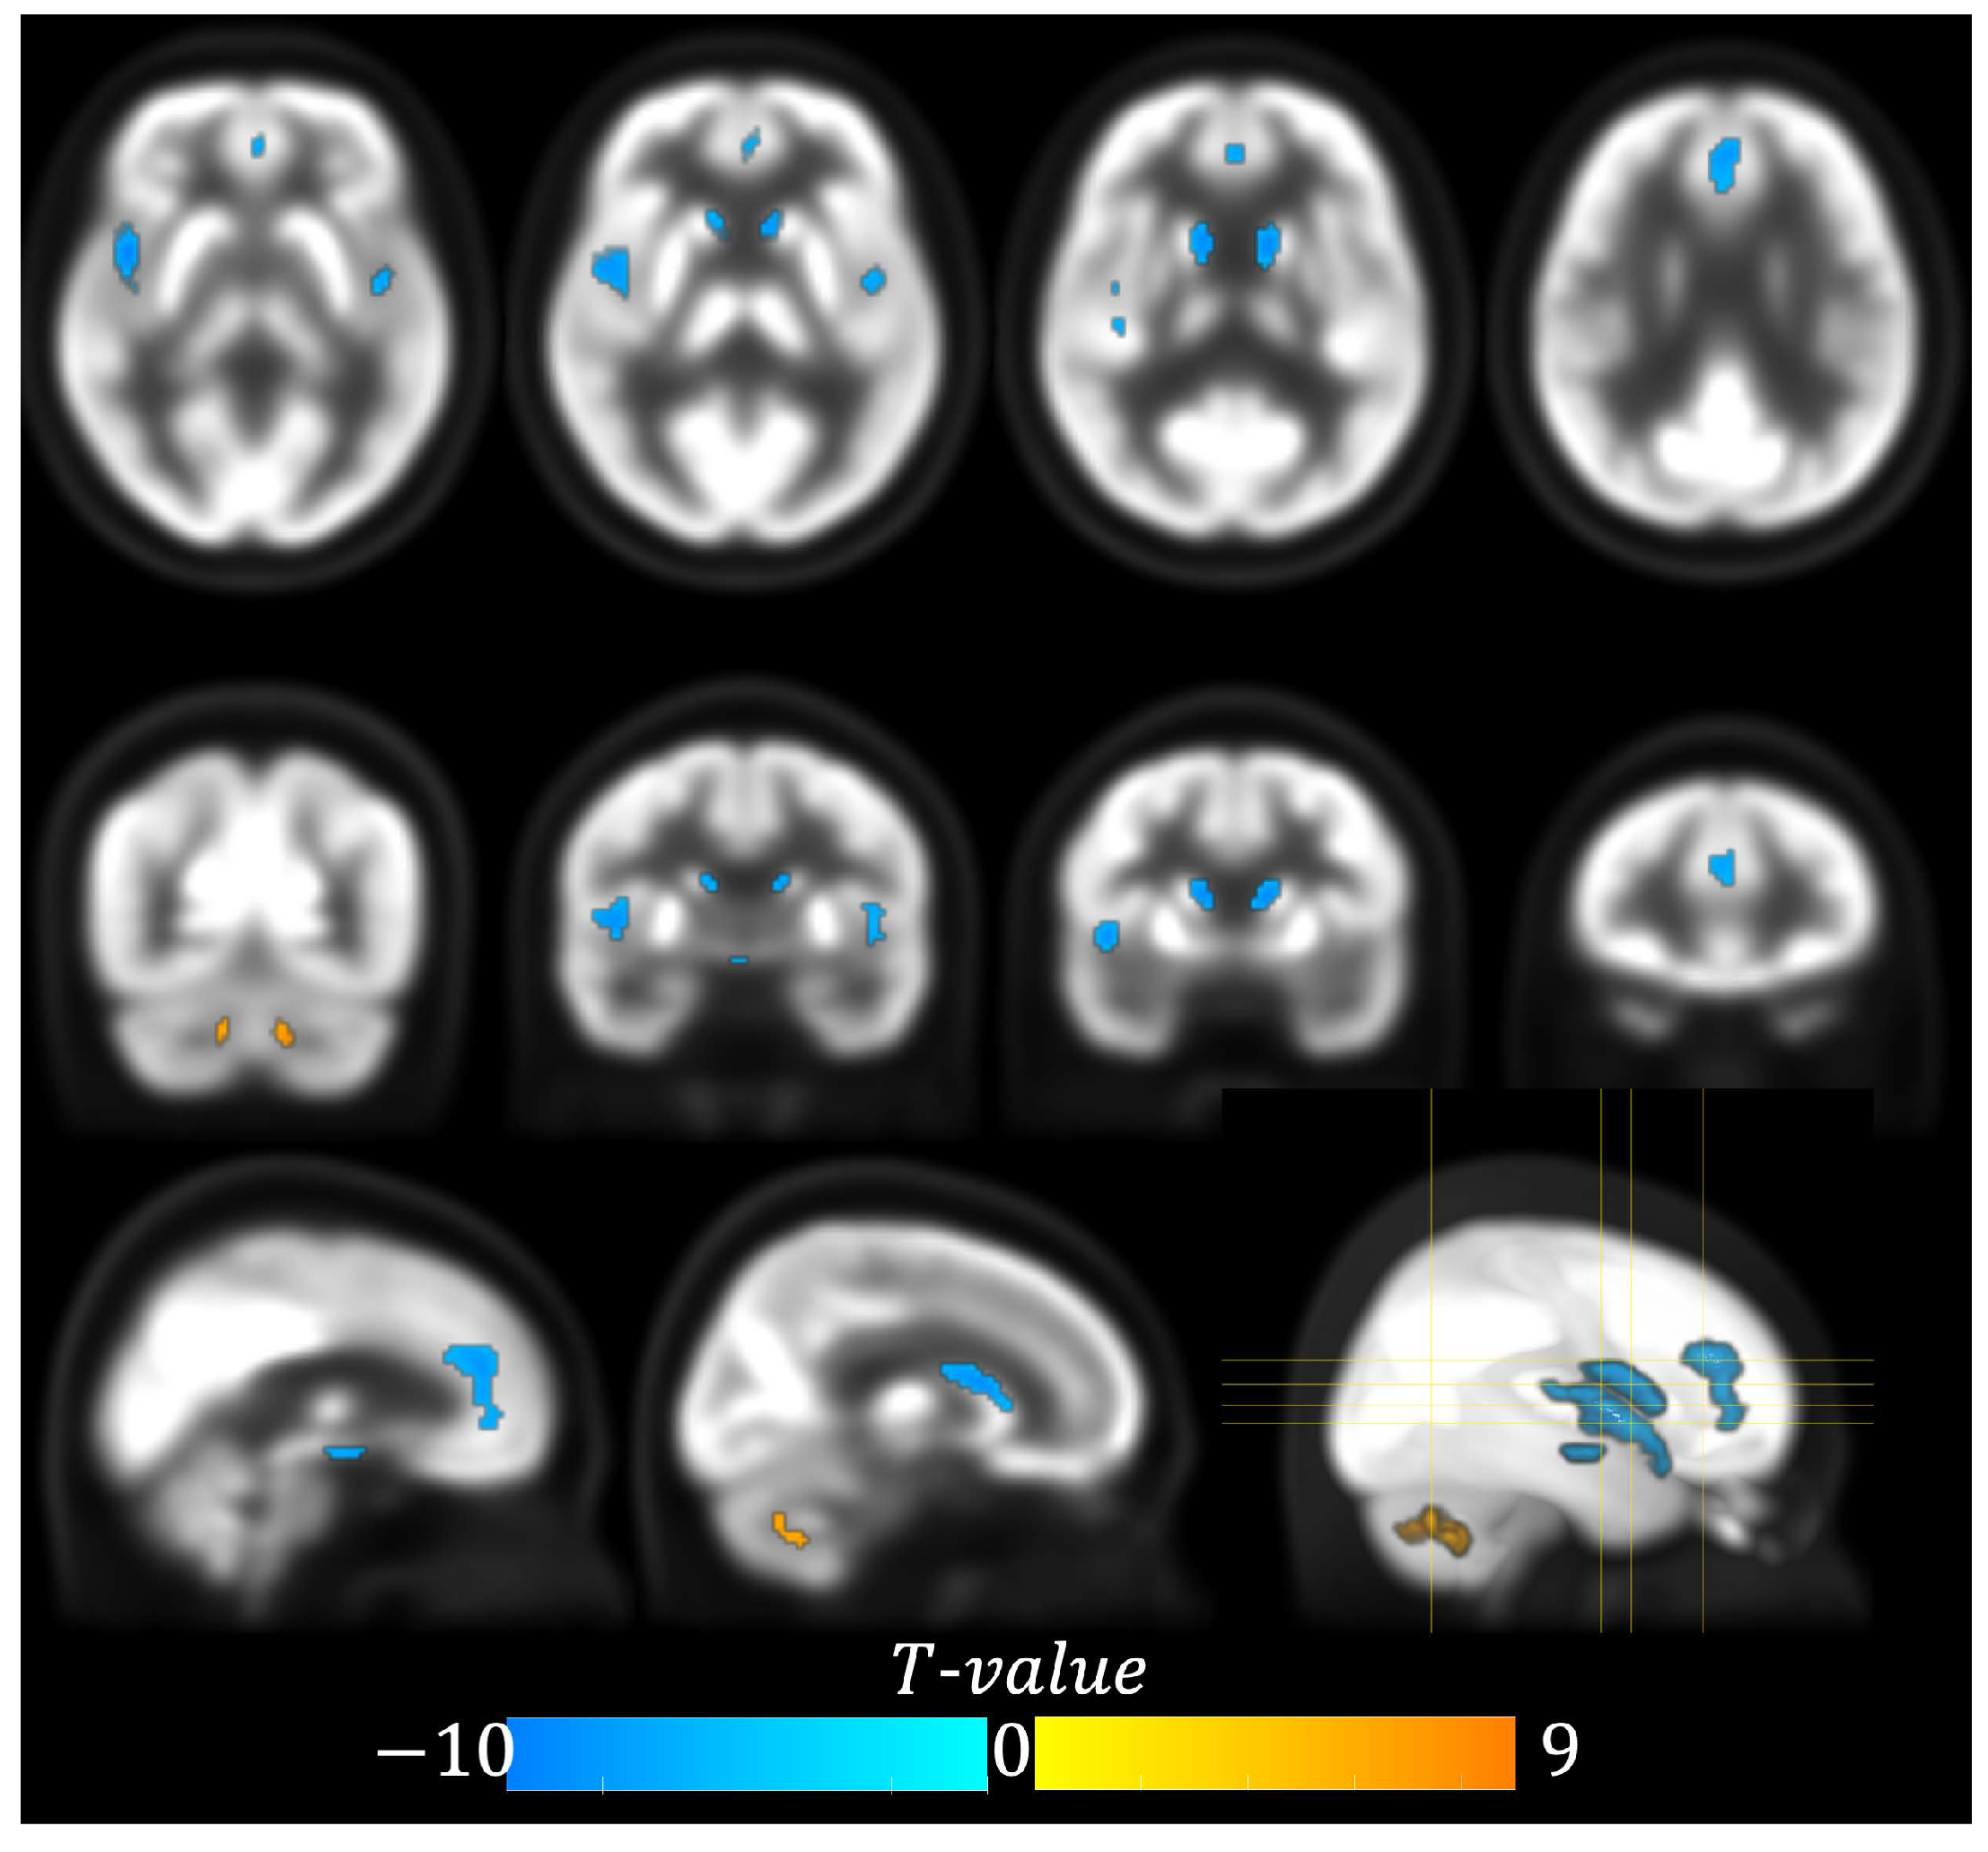

| Cluster | Anatomical Region | Cluster Size (#Voxel) | Peak Coordinates (x, y, z) Chinese2020 Space | Peak t-Value (df = 112) |

|---|---|---|---|---|

| 1 | Left Cerebellum 7b | 81 | −10, −60, −38 | 9.14 |

| 2 | Right Cerebellum 9 | 52 | 8, −46, −40 | 7.18 |

| 3 | Right Insula | 303 | 42, 8, −4 | −9.91 |

| 4 | Left Caudate | 159 | −12, 10, 10 | −9.23 |

| 5 | Right Caudate | 125 | 10, 12, 8 | −8.71 |

| 6 | Anterior Cingulate Gyrus | 215 | −2, 40, 16 | −7.43 |

| 7 | Left Insula | 72 | −42, −2, −4 | −7.45 |